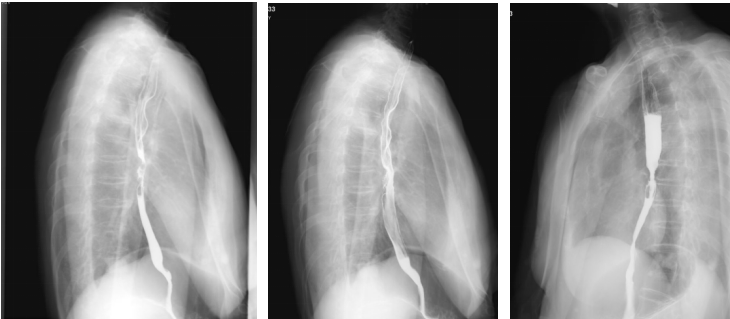

上消化道钡剂造影(2020-08-14):相当于胸7-9椎体水平的食道见范围长约35mm的狭窄段,管壁僵硬,粘膜皱襞破坏、中断,轮廓不光整,可见偏心性充盈缺损及小刺状龛影,狭窄段以上食管轻度扩张,对比剂排空延迟,余食道壁柔软,粘膜规则,未见充盈缺损及龛影,未见异常狭窄及扩张,贲门结构正常,开闭自如。

2021-01-15胃镜:距门齿26cm处食管局部黏膜苍白,见一纵行白色疤痕,局部无狭窄或新生物。

最佳疗效评估:2022-10-13胃镜:进镜至食管中段距门齿30cm处环形狭窄,所见食管上段黏膜充血水肿。